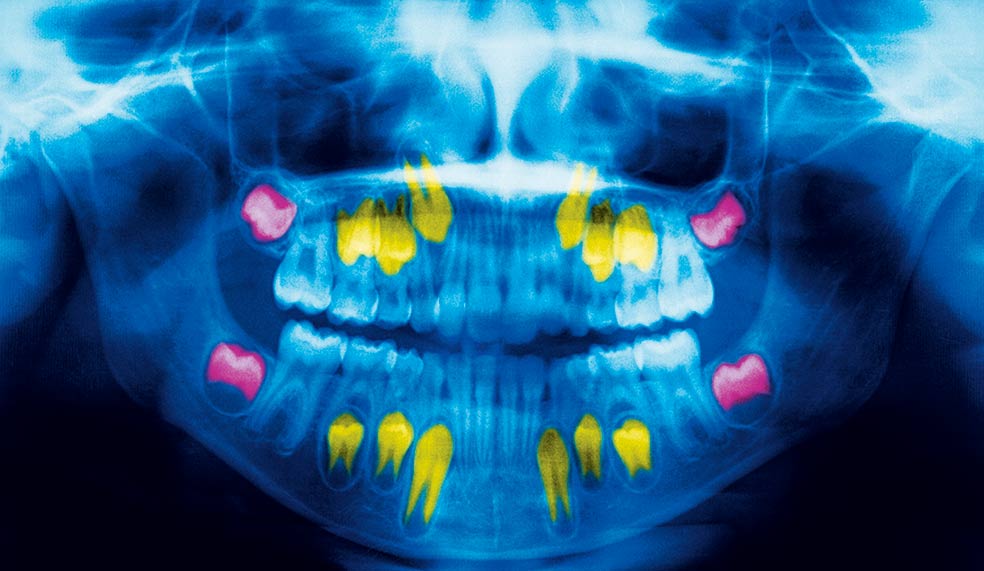

La formación de los dientes comienza antes de nacer, entre la sexta y la octava semana de desarrollo. Capas de esmalte van acumulándose, dejando marcas cada 6 o 12 días, que forman una serie de anillos concéntricos similares a los del árbol al crecer. Esos aros funcionan como biomarcadores que podrían permitir conocer la existencia de traumas o adversidades en la infancia o en fase fetal: pobreza familiar, un suceso traumático, un desastre natural...

Todo deja huella en las capas de esmalte. Esto permitiría anticipar la aparición de enfermedades. Por ejemplo, hay un aro negro en las capas interiores del esmalte que tenemos todos. Se conoce como 'línea neonatal' y corresponde con nuestro primer episodio estresante: el parto. Se sabe que episodios traumáticos y estrés crónico pueden dejar marcas físicas en el cuerpo y el cerebro.

Si la violencia u otro trauma o dificultad (léase guerra o desastre natural) ha aparecido en la infancia, durante el desarrollo de la estructura cerebral, es fácil que los niños crezcan con problemas cognitivos o emocionales o una mayor propensión a padecer cáncer o enfermedades coronarias. Para la investigadora Erin Dunn resulta importante contar con un indicador objetivo que muestre problemas psiquiátricos padecidos en la infancia. Y lo ha encontrado en los dientes que decenas de voluntarios le envían. Son analizados por rayos X y tomografía axial antes de cortarlos en finas 'rebanadas' que permiten analizar los anillos de esmalte. Y buscar huellas de eventos traumáticos.